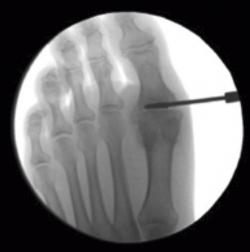

La posición de la artrodesis se determina utilizando la proyección de perfil con el Fluoroscan®, para evitar subluxaciones de la misma. Es con la visión de perfil cuando se colocan las agujas de Kirschner para los tornillos canulados y, después, se comprueba que la posición es correcta con la visión de frente. De forma percutánea, se colocan 2 agujas de Kirschner, una desde la primera falange y otra desde el metatarsiano en forma de X, cruzándose al nivel de la articulación (Figura 4). Es útil comprimir los dos huesos con la mano mientras se pasan las agujas.

figura-4.jpg

Figura 4. Los 3 portales necesarios para la artrodesis percutánea de la articulación metatarsofalángica del primer dedo. El portal más proximal y el más distal se utilizan para la introducción de los tornillos canulados.